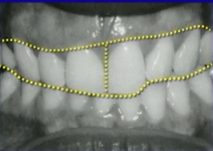

The patient I’m going to use as an example is pictured. Before the seating appointment, she had undergone two years of orthodontics to intrude the right canine, lateral, and central, which had significant wear and were over-erupted. I then prepped all six anterior teeth for veneers.